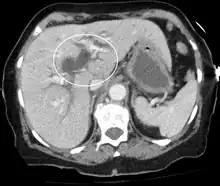

Imaging

Medical imaging such as ultrasound, CT scan, and HIDA scans are useful for detecting bile duct blockage.[12]